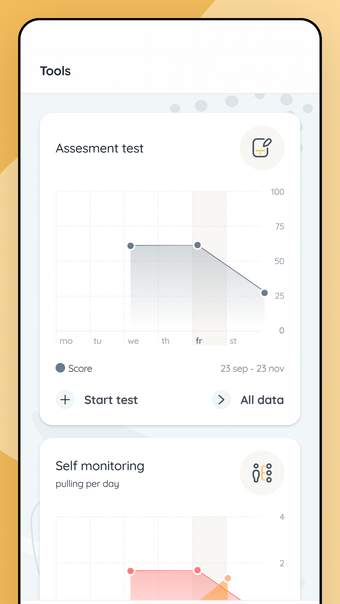

TrichStop Trichotillomania App - это бесплатное программное обеспечение для iPhone, которое является частью категории "Медицина".О приложении TrichStop Trichotillomania для iPhone

Приложение TrichStop Trichotillomania доступно для iOS 16.4 или выше. Текущая версия программы - 3.1.0, и вы можете запустить ее только на английском языке.